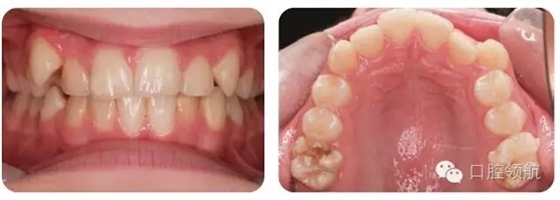

圖2.10的上頜牙列特征有哪些?

圖2.10

早期恒牙列患者,UL3腭側(cè)錯(cuò)位萌出。左上頜乳尖牙滯留。UR6輕度發(fā)育不全。

治療方法

拔除滯留且阻擋恒牙的乳尖牙。